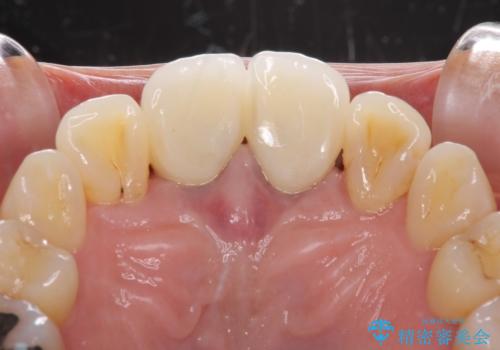

前歯はオールセラミッククラウンに補綴することとしました。

審美面と合わせて清掃性も改善され、患者様には大変満足していただきました。